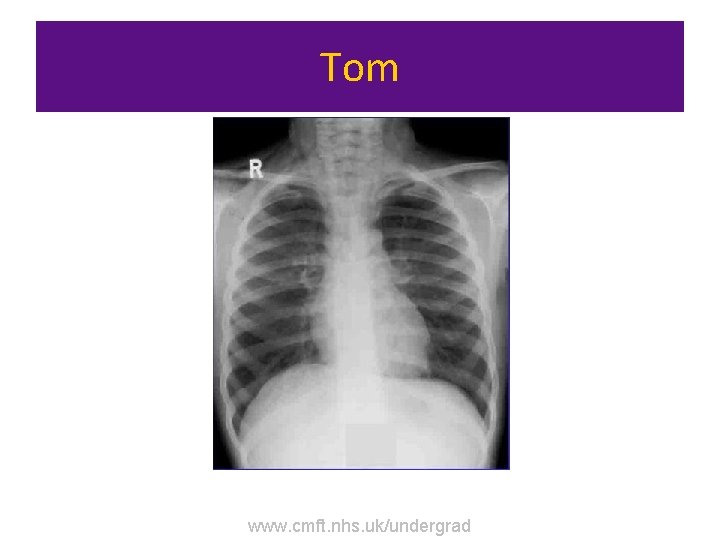

Tom • Tom is a 22 year old male. He has presented to A&E with shortness of breath and an audible wheeze • BP 135/90, T 36. 5. RR 38 • Review the investigations provided. You will then be asked questions on diagnosis and initial management. www. cmft. nhs. uk/undergrad

Tom • • Hb 11. 0 (9. 0 – 13. 0) Wcc 6. 0 (4. 0 – 11. 0) Plt 250 (150 -400) Na 139 (135 -145) K 4. 5 (3. 5 -5. 5) Ur 5. 9 (3. 3 -6. 6) Cr 80 (80 -120) • ABG on 15 L oxygen via non-rebreath mask • • • p. H 7. 32 (7. 35 -7. 45) PCo 2 5. 9 (4. 5 -6. 0) PO 2 9 (10 -12 in air) HCO 3 23 (22 -26) BE -3 (-2 - +2) www. cmft. nhs. uk/undergrad

Tom www. cmft. nhs. uk/undergrad